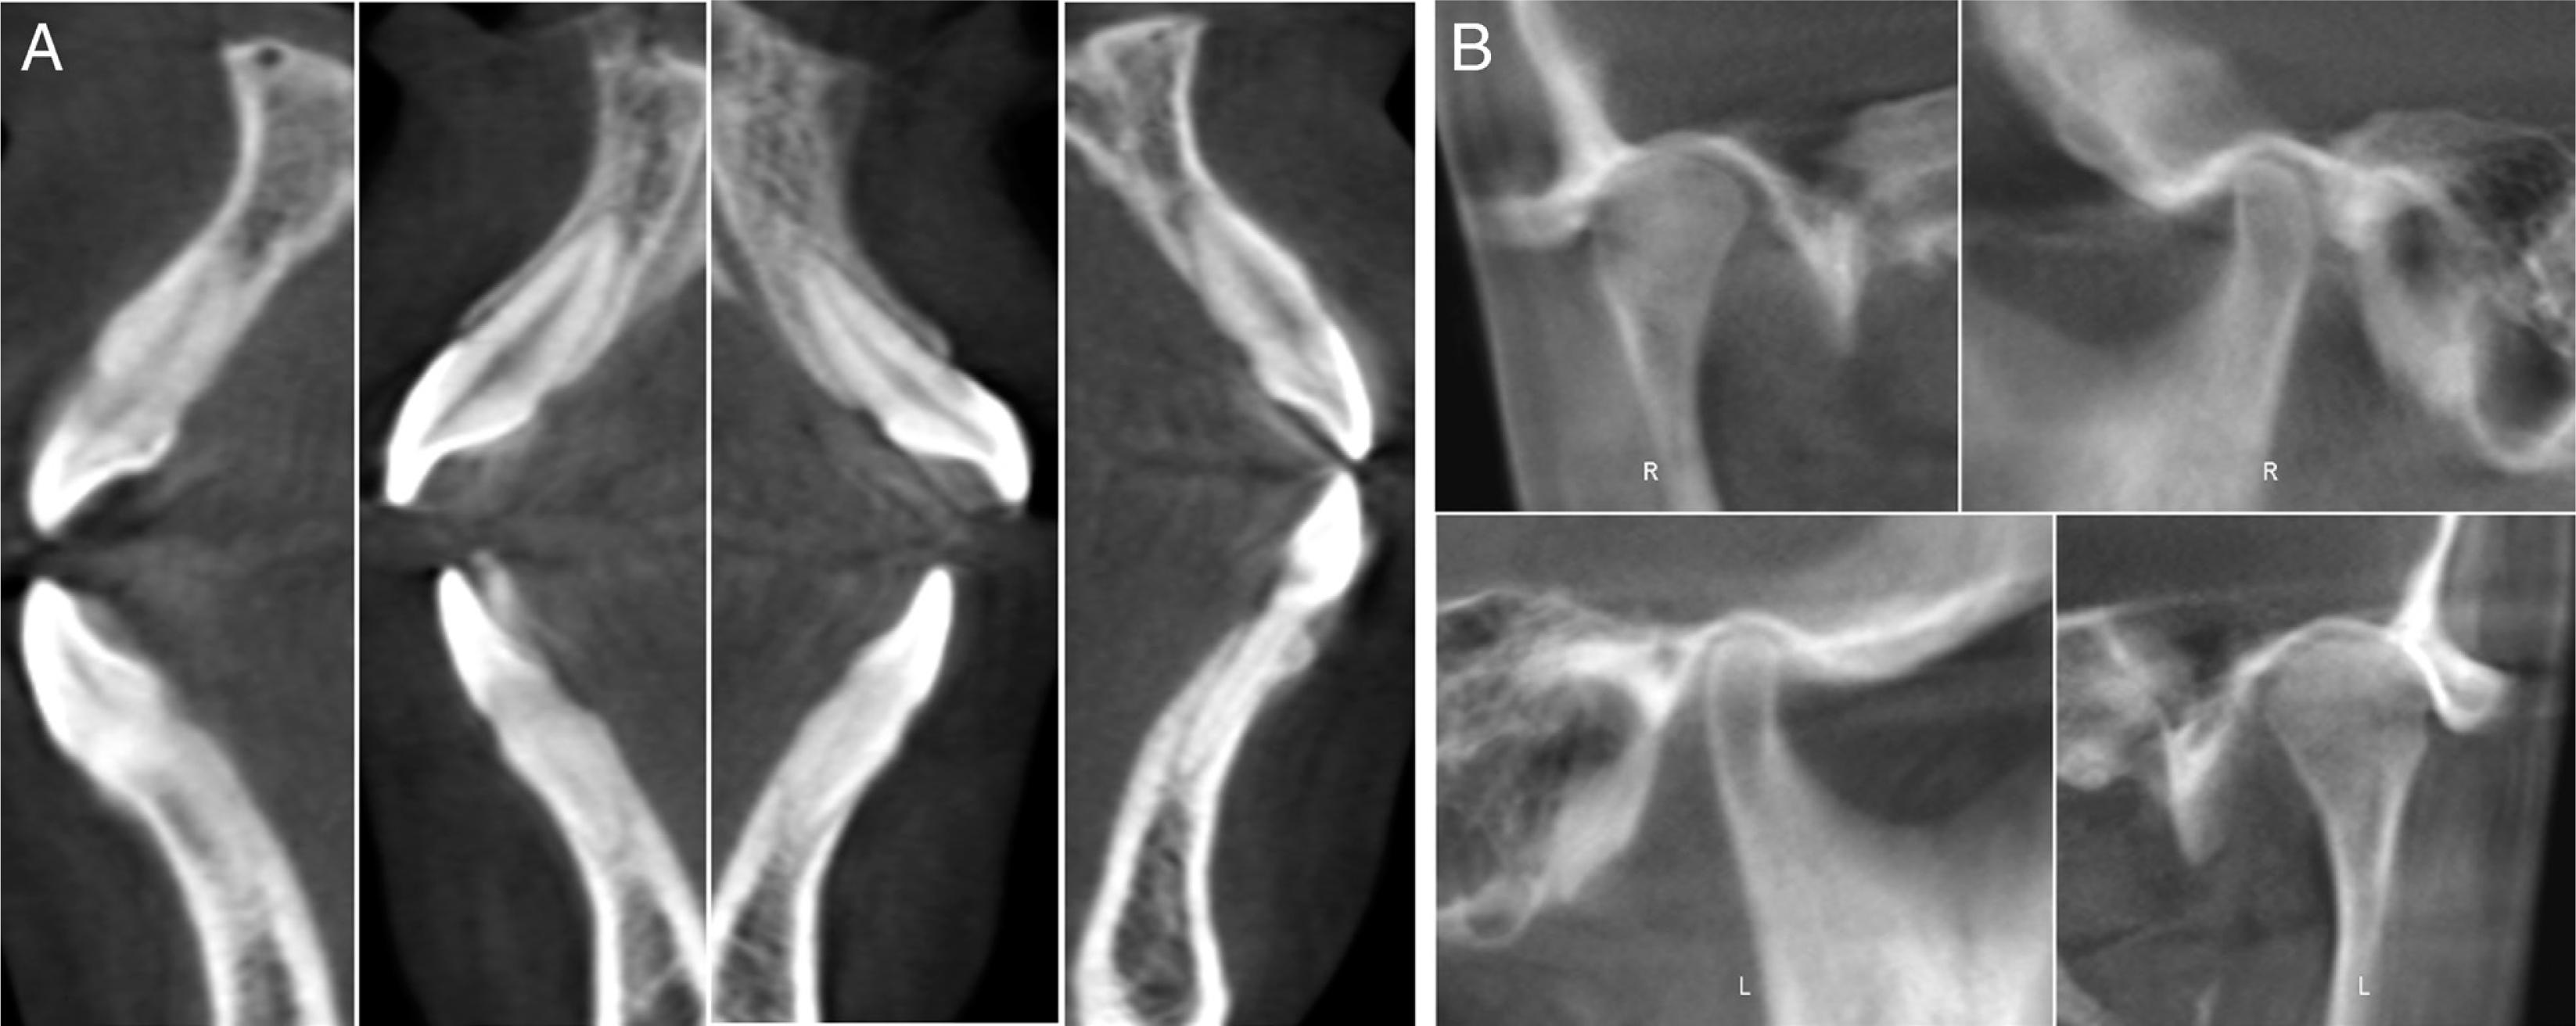

Figure 2.